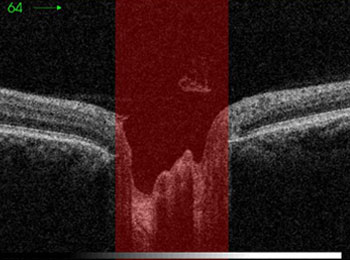

Vision altérée par un glaucome grave

Vision altérée par un glaucome débutant

Vision altérée par un glaucome très grave